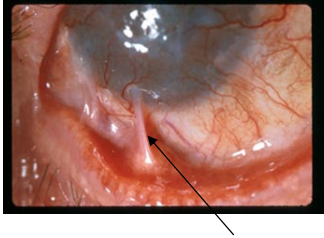

64 一老婦人,自年輕起眼睛即長年有分泌物,眼痛澀,患者一直未接受治療,求診時如圖箭頭所示, 下列敘述何者正確?

(A)上胞下垂,瞼輪黏合 (B)漏睛症過久,毒邪鬱積,黏合而成 (C)邪毒久鬱,脈絡鬱阻,胞瞼重壅而成 (D)毒邪損及胞瞼與白睛表層,使瞼肉與白睛黏著,阻礙眼睛轉動,為椒瘡之後遺症